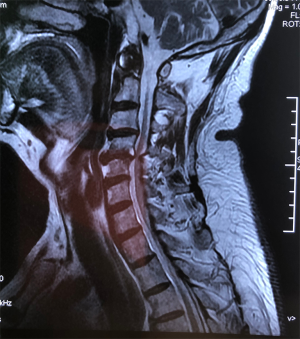

A 12-year-old boy with a chief complaint of neck and shoulder pain for more than 2 years presented to our hospital. The patient was neurologically intact, and the physical examination showed a limited cervical range of motion. Although the hyperflexion-extension plain film examination showed no instability, an increase in the ratio of PAOI (PAOI = ~1) and extremely small PAOI distance were observed. In addition, the patient was found to have cervical curvature changes and mild cervical disc degeneration on MRI scans. Conservative treatment was initiated.